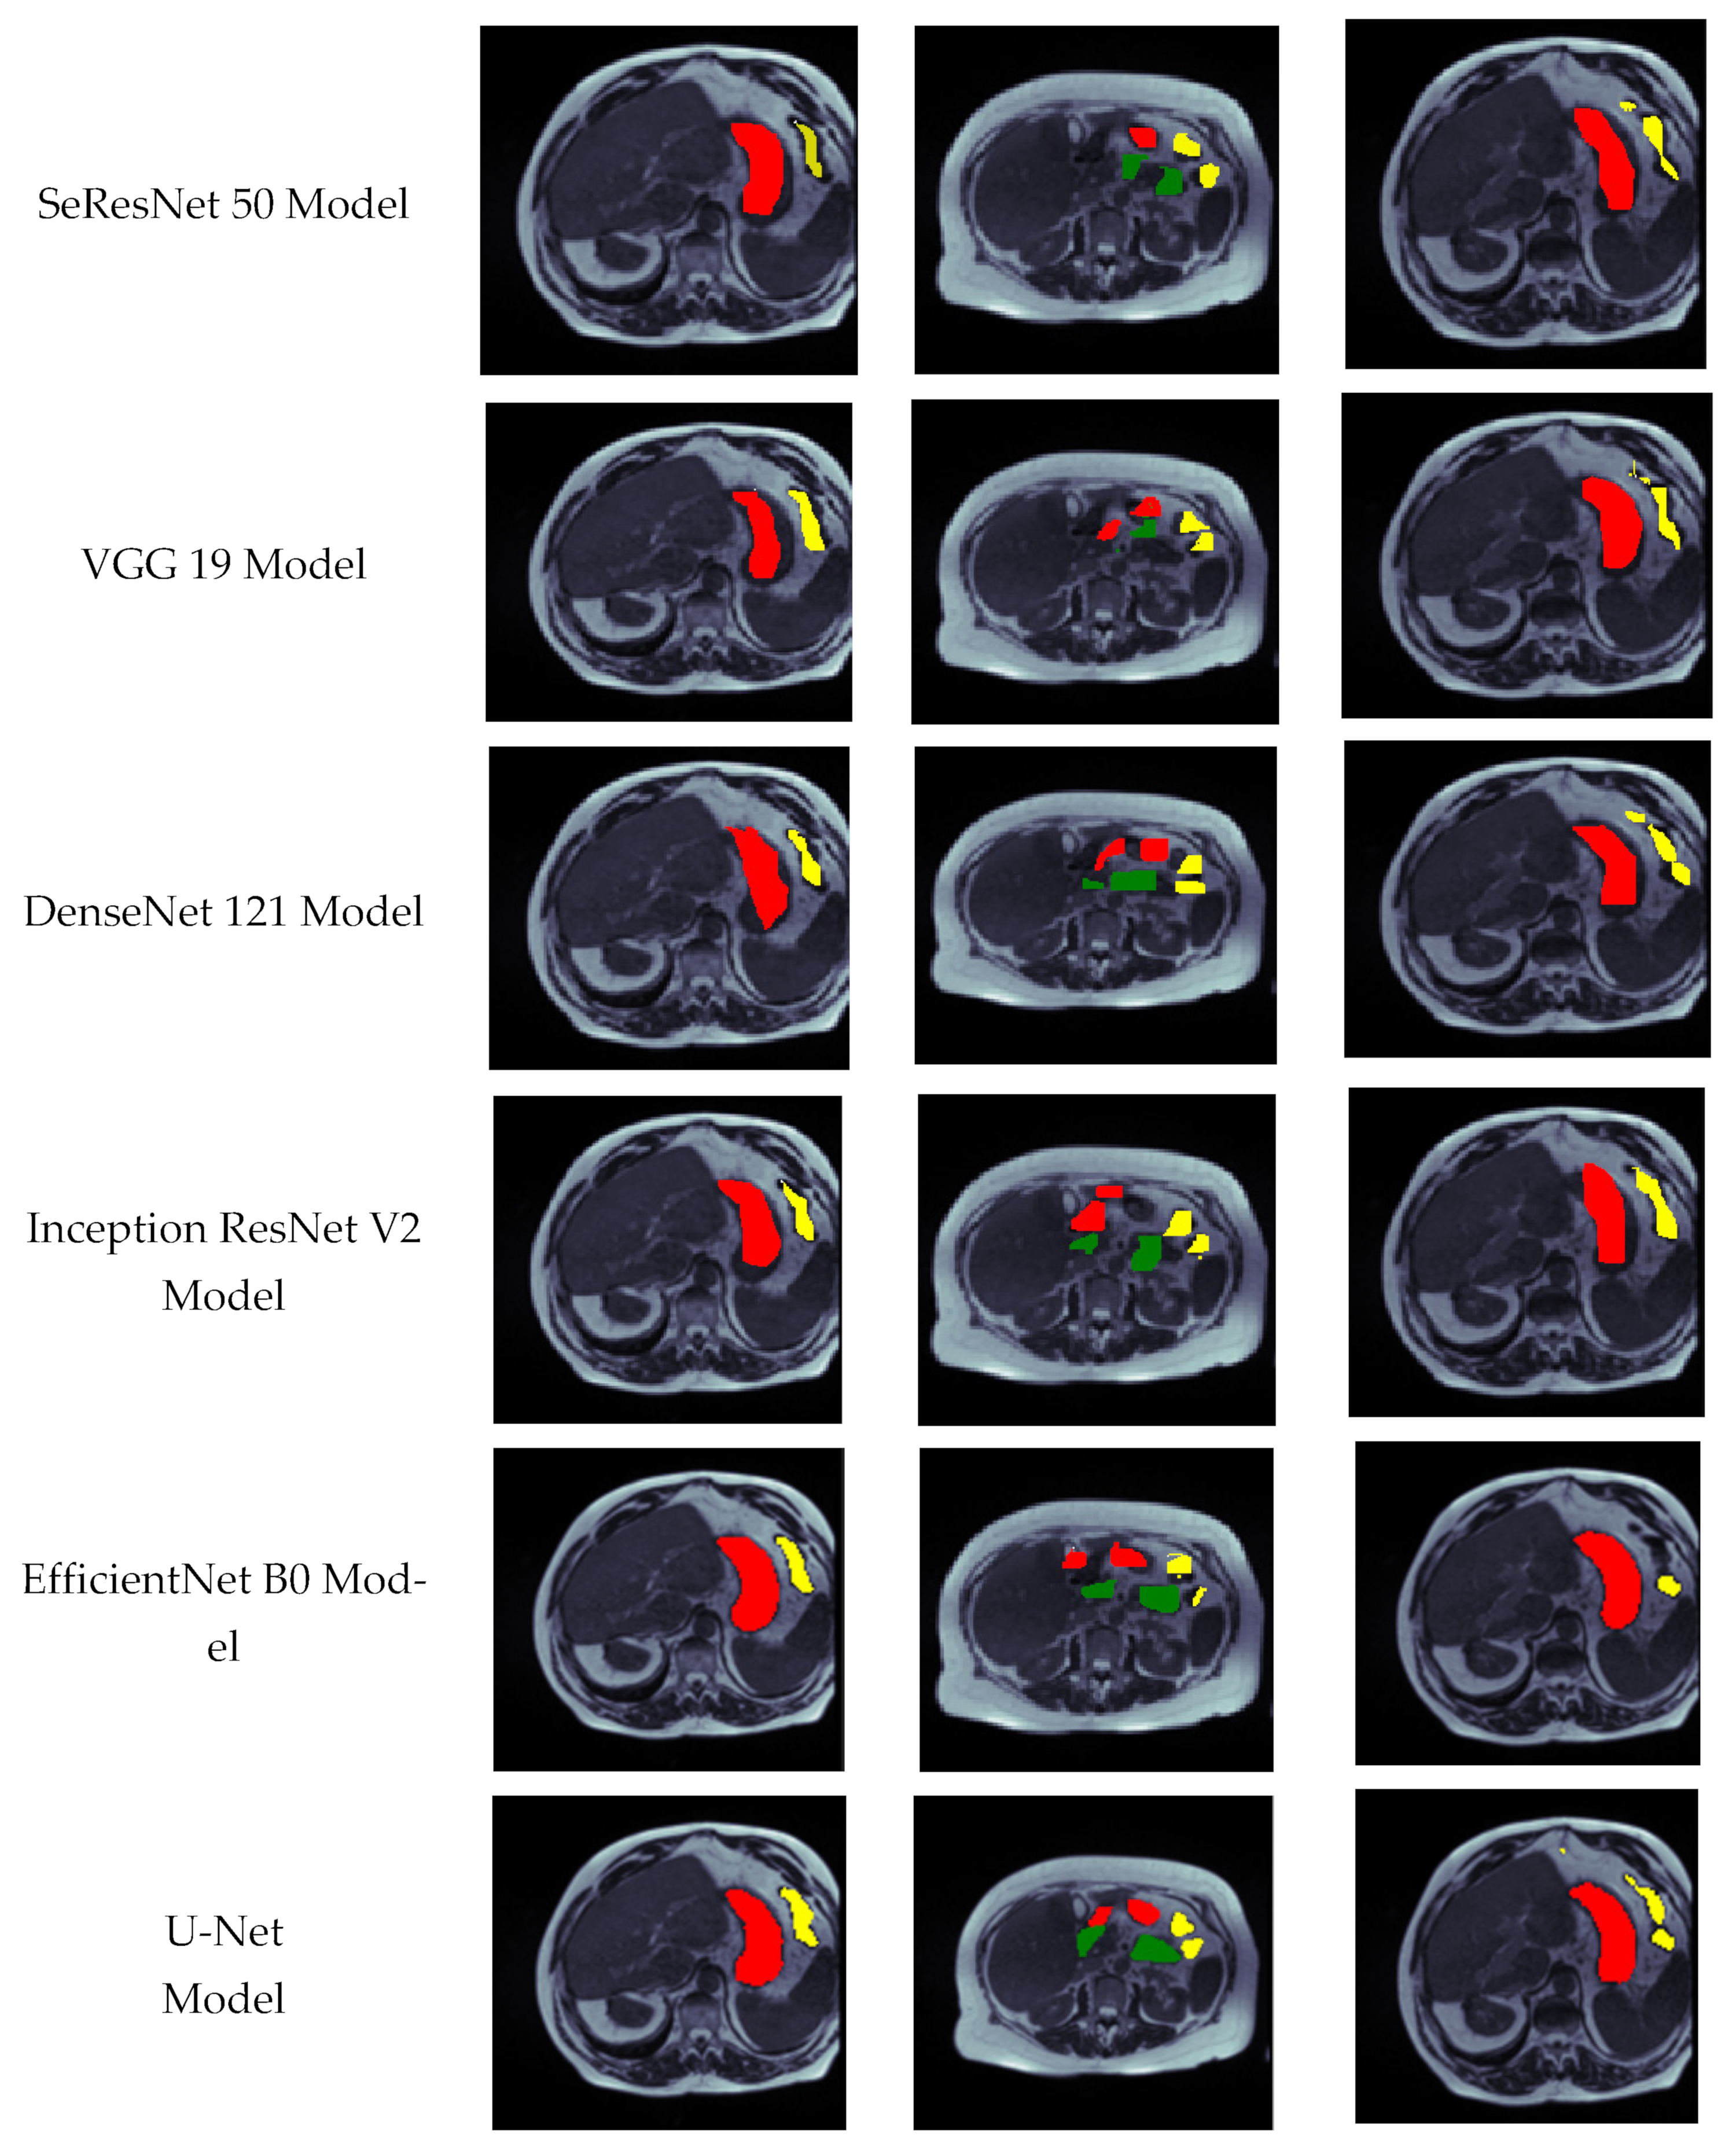

4.5. Visual Analysis of Segmented Images